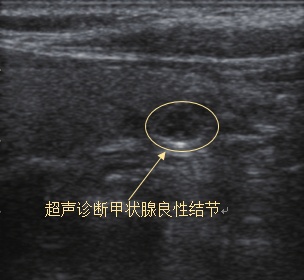

一旦确诊甲状腺结节,我们普通人最担心的问题就是这个结节是不是癌。事实上,尽管临床上甲状腺结节的检出率很高,但是只有5%的甲状腺结节是甲状腺癌。判断甲状腺结节的良恶性有多种方式,其中最常用也是首选的是甲状腺超声检查。很多病人也是因为超声检查发现了结节,再进一步做其他检查明确诊断的。

结节的大小并不是判断良恶性的标准,主要还是结合超声检查报告中的描述,若包含以下几点,提示恶性的可能性就比较大:①微小钙化(砂砾状钙化、针尖样或簇状分布的钙化等);②边缘不规则(边界模糊/微分叶);③纵横比>1;④实质性、低回声或极低回声结节;⑤结节内或周边血流丰富(TSH正常情况下);⑥有颈部淋巴结异常等。

对于普通人来说,通过描述不太容易判断结节的性质,如果超声报告上同时打有TI-RADS分类,那么我们可以从这个分类判断结节的性质。TI-RADS分类(见下表)按0~6类对甲状腺结节进行分类,如果分级在4类以上,说明恶性可能性大,需要及时与医生沟通。